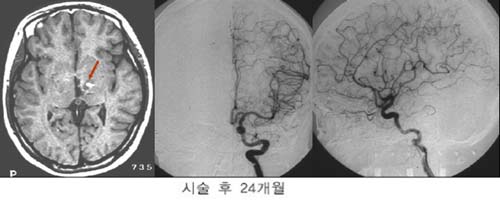

°æ·ÃÀ»

ÁÖ¼Ò·Î ÀÔ¿øÇÑ È¯ÀÚÀÇ MRI ¹× ³úÇ÷°üÃÔ¿µ¼ú

»çÁø.

µ¿Á¤¸Æ±âÇüÀÇ

Å©±â°¡ Ä¿¼ ¼ö¼úÀÇ À§Ç輺ÀÌ ³ô¾Æ °¨¸¶³ªÀÌÇÁ¸¦

°èȹÇÏ¿´´Ù. º´º¯ÀÇ Å©±â°¡ Ä¿¼ °¨¸¶³ªÀÌÇÁ

¹æ»ç¼±¼ö¼úÀ» ¸îÂ÷·Ê¿¡ ³ª´©¾î¼ ½ÃÇàÇÏ·Á

ÇÏ¿´À¸³ª ÇÑÂ÷·ÊÀÇ °¨¸¶³ªÀÌÇÁ ½Ã¼ú ÈÄ

24°³¿ù° ¸ðµÎ ¿ÏÄ¡µÇ¾ú´Ù.

º´º¯ÀÇ

Å©±â°¡ Å« µ¿Á¤¸Æ±âÇüÀÇ °æ¿ì °¨¸¶³ªÀÌÇÁ

¹æ»ç¼±¼ö¼úÀ» ¸îÂ÷·Ê¿¡ ³ª´©¾î¼ ½ÃÇàÇÏ¿©¾ß

Çϳª ÀϺΠȯÀÚÀÇ °æ¿ì ÇÑÂ÷·ÊÀÇ °¨¸¶³ªÀÌÇÁ

½Ã¼ú·Îµµ ¿ÏÄ¡¸¦ º¸¿´´Ù